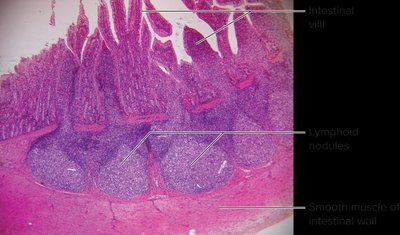

Lymphoid tissue consists of aggregations of lymphocytes in connective tissues and mucous membranes, especially in areas exposed to external environments.

Mucosa-Associated Lymphoid Tissue (MALT): Found in respiratory, digestive, urinary, and reproductive tracts.

MALT: Aggregates of lymphoid tissue in mucous membranes.